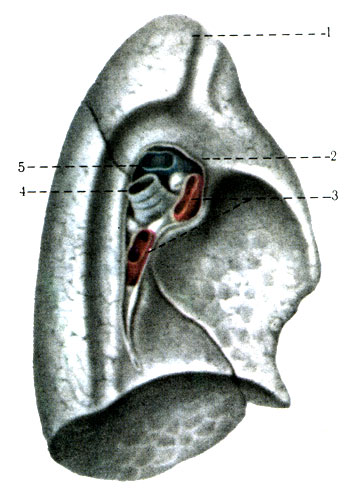

Анатомические изображения сегментов легких различных животных

Раздел: Другие животные